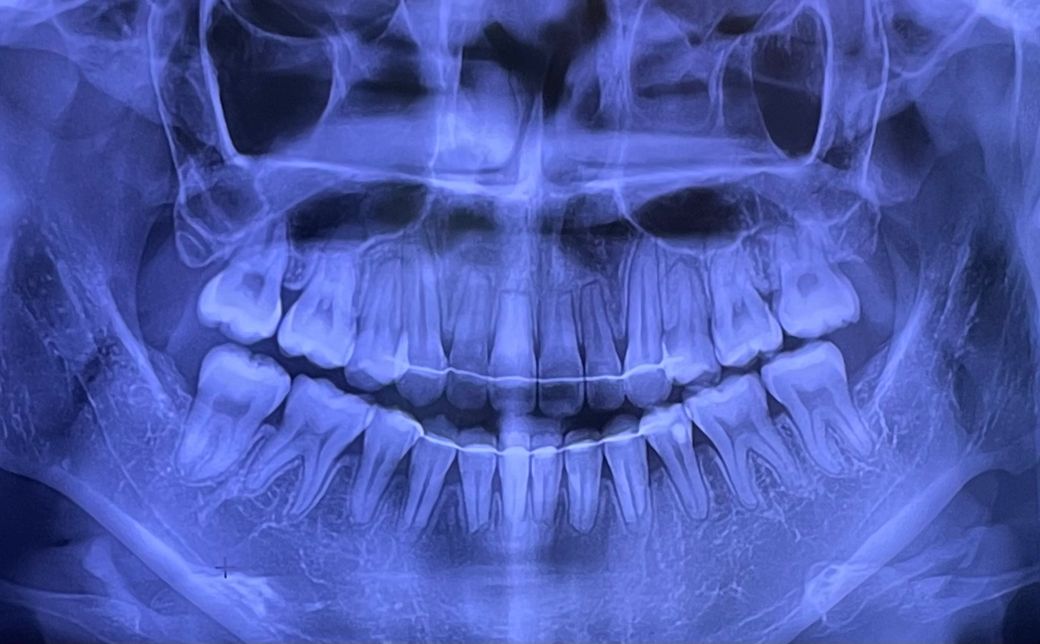

왼쪽 윗 어금니 인레이 충치치료를 했는데 이제 아랫쪽도 시려요ㅠㅠ 사진상 충치가 있나요??왼쪽 아래 어금니를 눈으로 보면 점 크기의 충치가 보이긴해요

엑스레이 상으로는 시릴정도로 충치가 잇어 보이진 않습니다. 잇몸이 안좋거나 치경부 마모증때문에 그럴수 있습니다.

점 크기 정도의 초기 충치는 엑스레이상에선 관찰이 어렵습니다 오히려 육안으로 보고 판단합니다